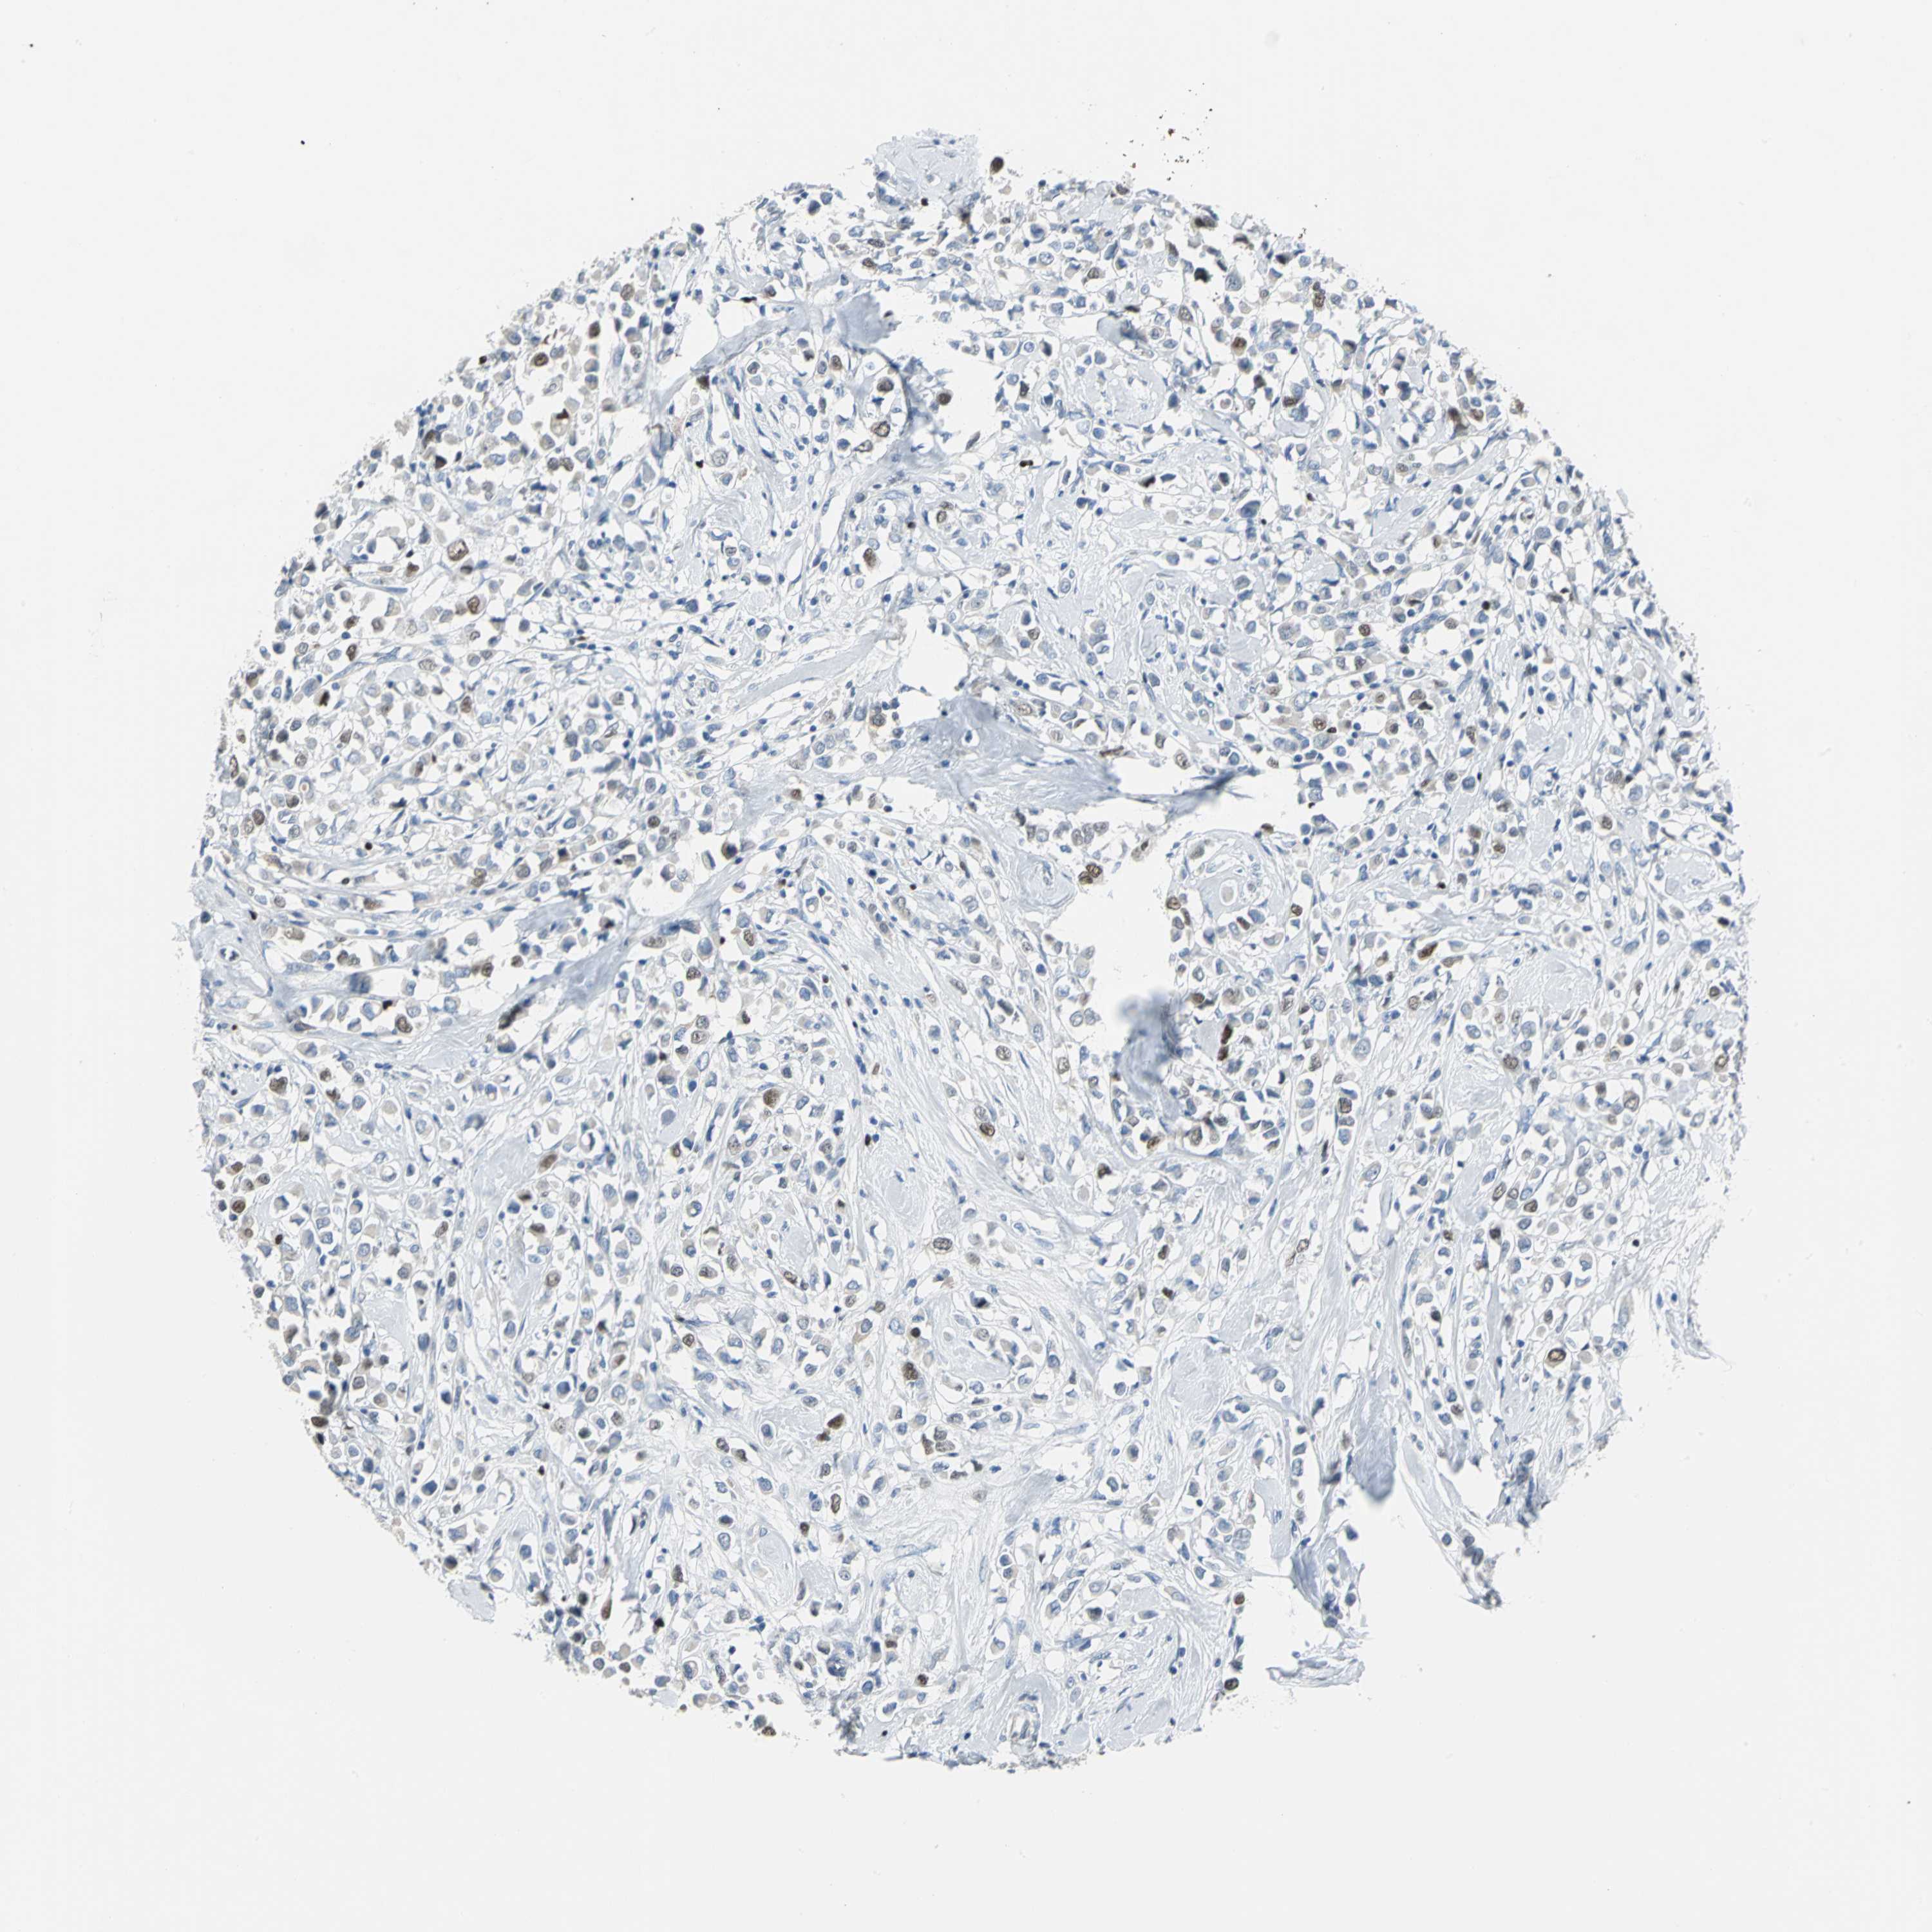

BRCA TCGA BRCA VALIDATION PROTEIN EXPRESSION

ANTIBODIES

AND

VALIDATION